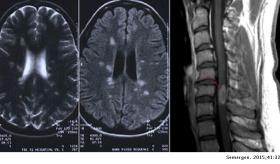

Las radiografías permiten que los médicos verifiquen la existencia de cambios en las articulaciones y los huesos, también conocidos como espondiloartritis axial radiográfica, aunque los signos visibles de la espondilitis anquilosante, también conocida como espondiloartritis axial, pueden no manifestarse al principio de la enfermedad.

Una resonancia magnética usa ondas de radio y un campo magnético potente para brindar imágenes más detalladas de los huesos y los tejidos blandos. Las imágenes por resonancia magnética pueden revelar evidencia de espondiloartritis axial al principio de la enfermedad, pero son mucho más costosas.